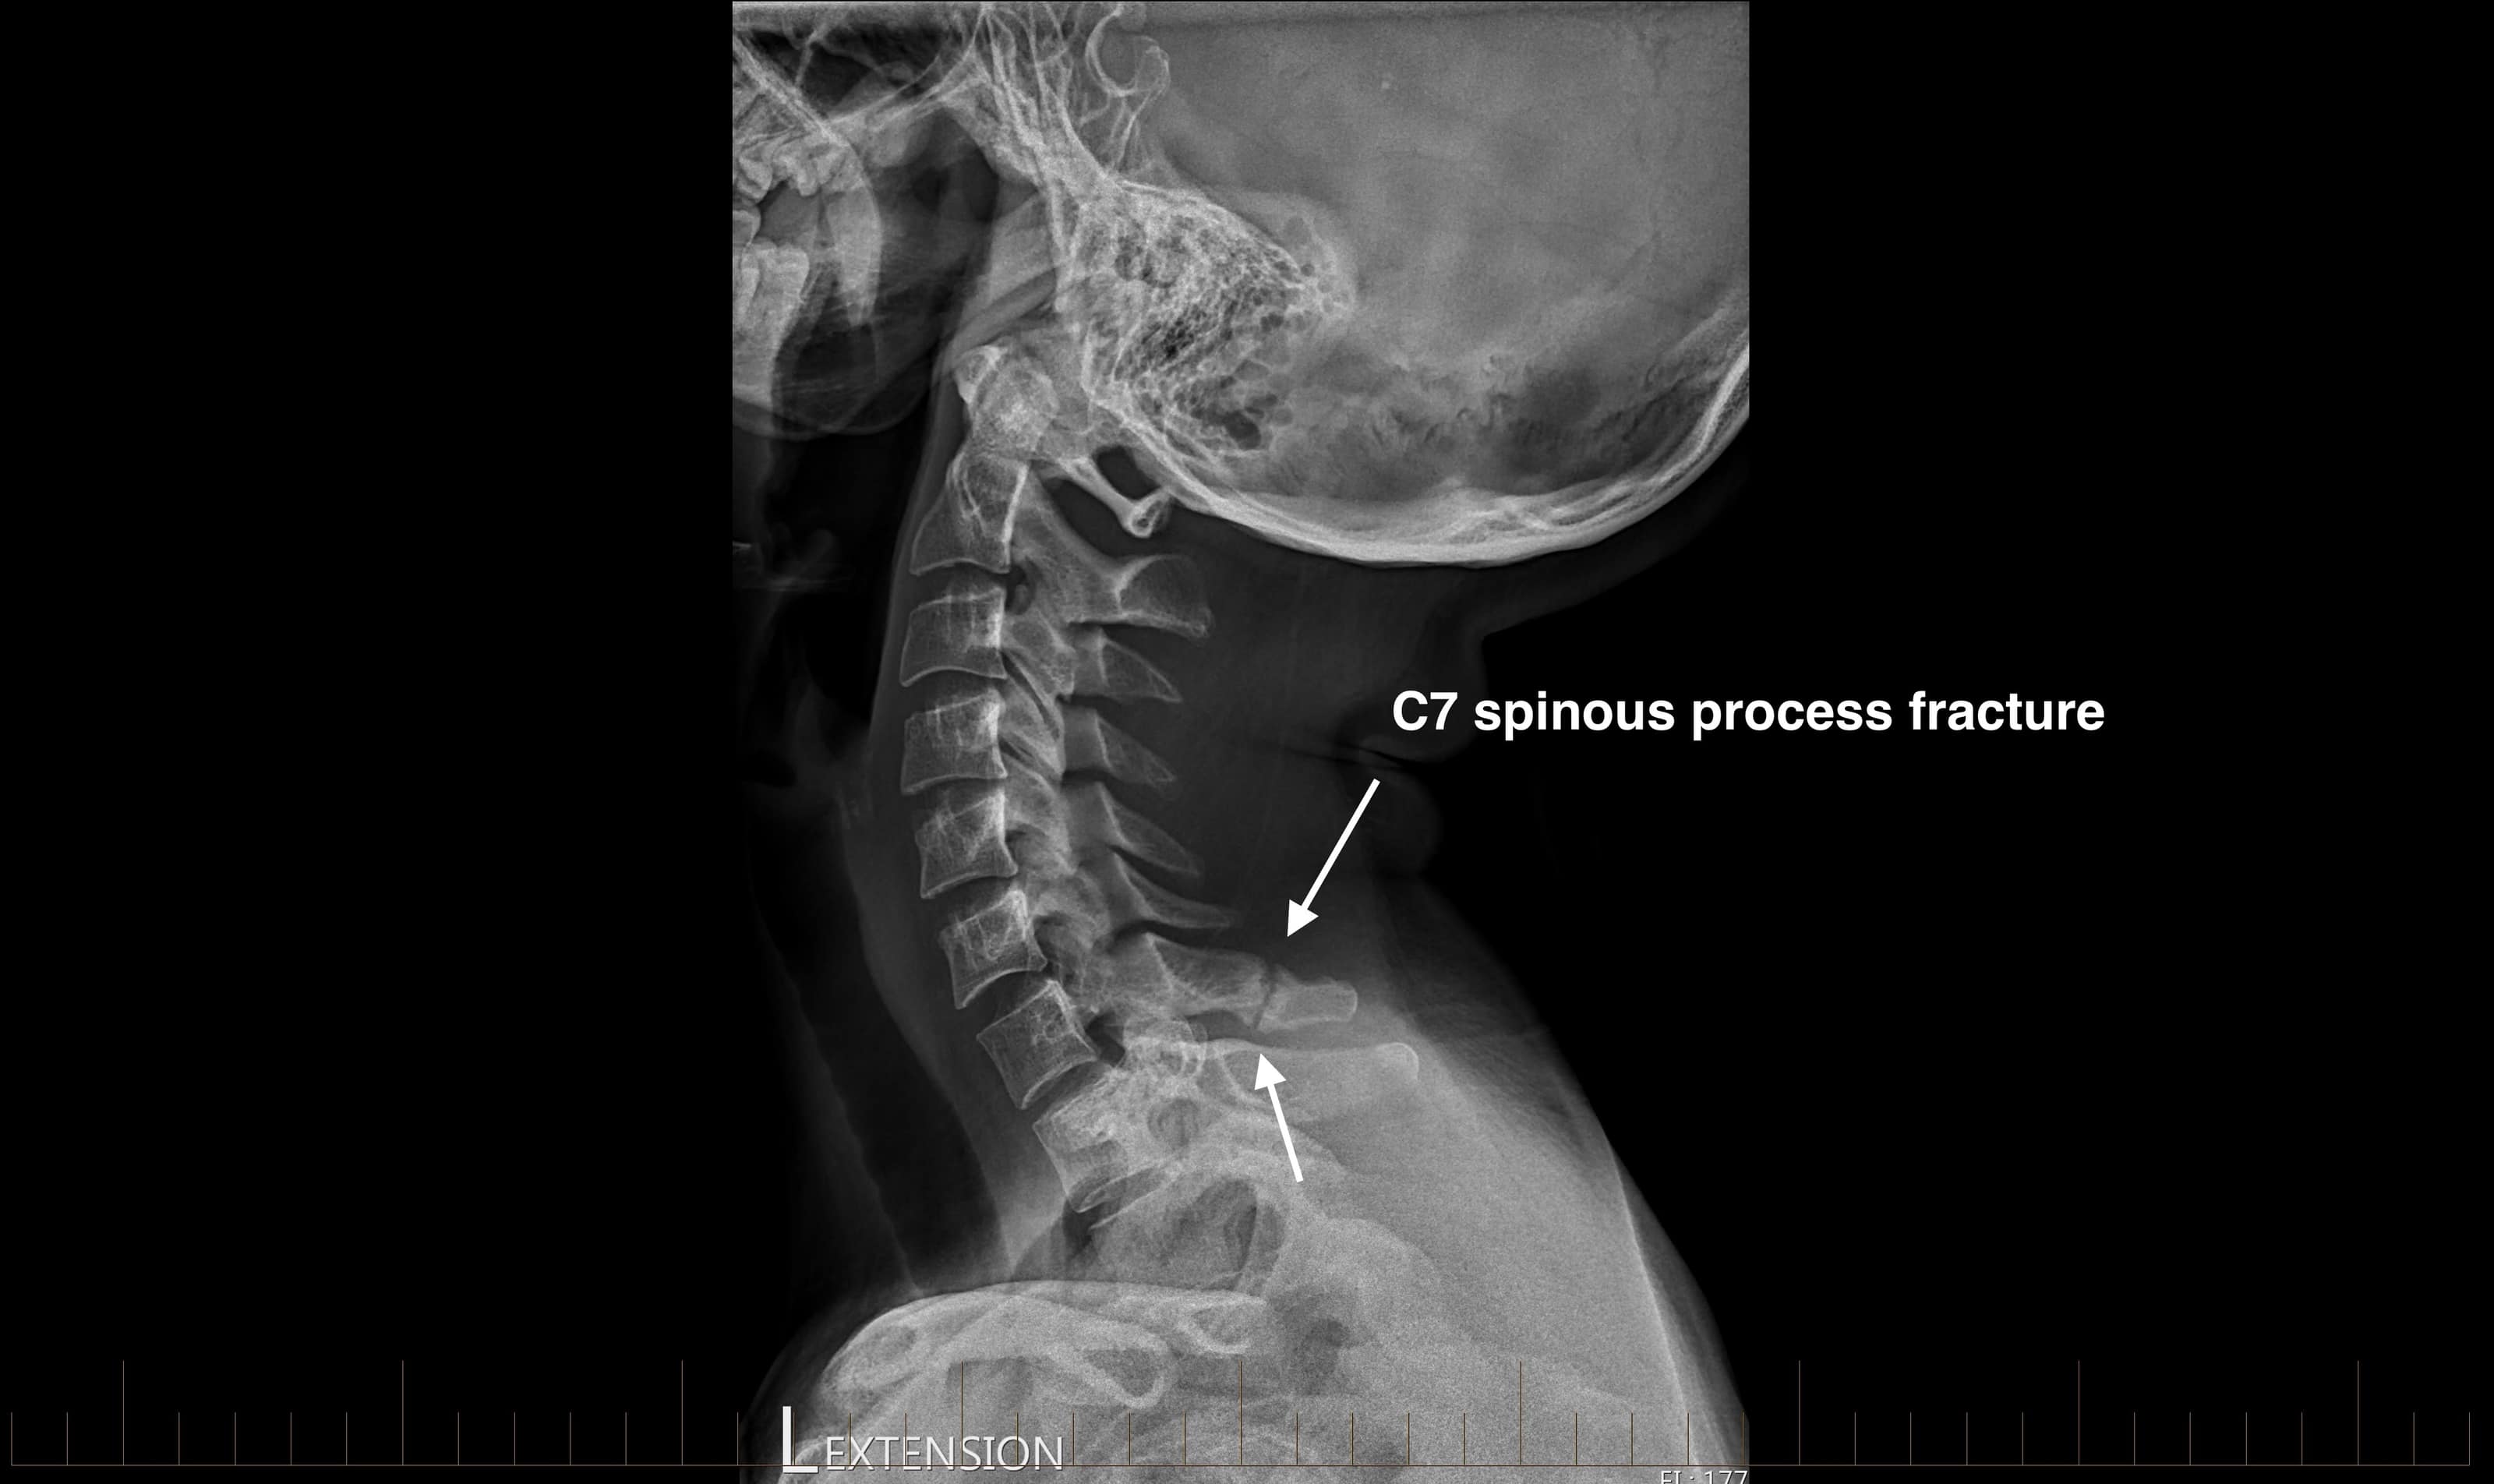

Radiology Review C7 Spinous Process Fracture Axis Sports Med Remote Fracture On X Ray The role of concurrent injuries in patients treated for. Distal radius fracture (drf) is a common fracture of the upper extremity. They may be divided into (1) “high energy trauma fracture,” (2) “fatigue. Distal radius fracture (drf) is a common fracture of the upper. The process of healing is different depending on the configuration of the fracture fragments and can. Remote Fracture On X Ray.